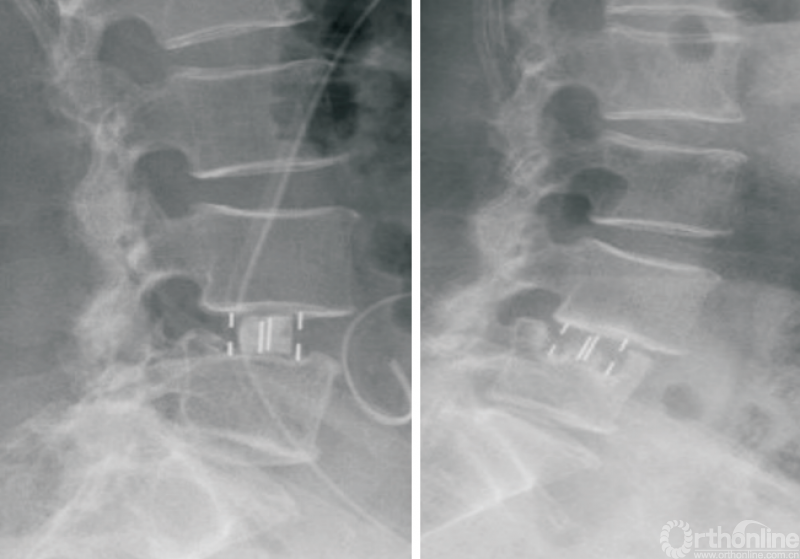

2.4 L5/S1 OLIF

L5/S1节段因血管与腰大肌间隙较窄,过去被认为是OLIF手术的相对禁忌证,但是,越来越多的研究证实,L5/S1 OLIF(图8)是安全可行的,且相较于其他节段,并不会明显增加并发症的发生率或延长住院时间[2,45]。但是,L5/S1 OLIF需要评估血管位置。

图8 L5/S1 OLIF技术

国内第一例L5/S1 OLIF手术于2021年6月在浙江大学医学院附属邵逸夫医院由脊柱外科团队完成,迄今为止已完成了数例该术式,未发生血管损伤、肠梗阻等并发症,其余远期并发症如融合器沉降等尚在随访中。